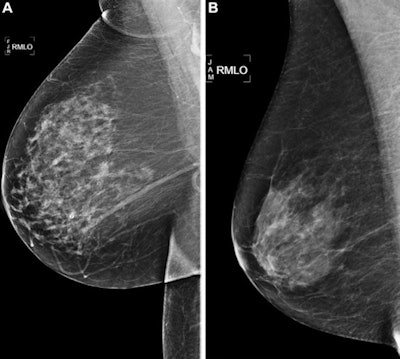

Mammography AI algorithms perform better than risk models for predicting breast cancer risk at zero to five years when using a negative screening exam, suggest findings published June 6 in Radiology.

Although several risk models are employed to guide breast cancer screening and prevention strategies, the researchers pointed out that they are only moderately successful at determining risk. However, AI's ability to extract imaging biomarkers may hold promise in predicting risk beyond just clinical factors used by current risk models. The authors noted that to their knowledge, there's a lack of data exploring AI's potential at predicting risk for shorter times over which risk is assessed.